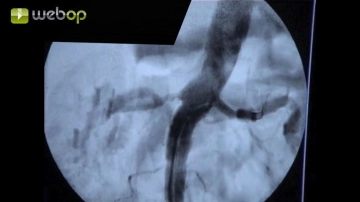

Advance a Terumo® guidewire through the sheath and introduce a pigtail catheter into the suprarenal aorta. Perform survey angiography of the aorta and renal artery in road-mapping technique. Angiography reveals bilateral subtotal stenosis of the renal arteries close to their origins. Next, in this mask place a Renal Double Curve (RDC) catheter into the suprarenal aorta. Slowly retract the guidewire until it slips into the infundibulum at the origin of the left renal artery. Once the guidewire is seated securely, exchange the Terumo® guidewire for a soft-tipped thinner, but harder, metal wire, advancing it carefully into the peripheral renal artery.

This involves the administration a small bolus of contrast agent to visualize the abdominal aorta as a roadmap. This image is saved as a mask. Subsequent images are then acquired without contrast media and subtracted from the mask. In this way, for example, only the current position of a radiopaque catheter will be displayed. In the resulting subtraction images, the bright catheter will be visible against the dark background of the abdominal aorta, and any background irrelevant to this study is omitted.